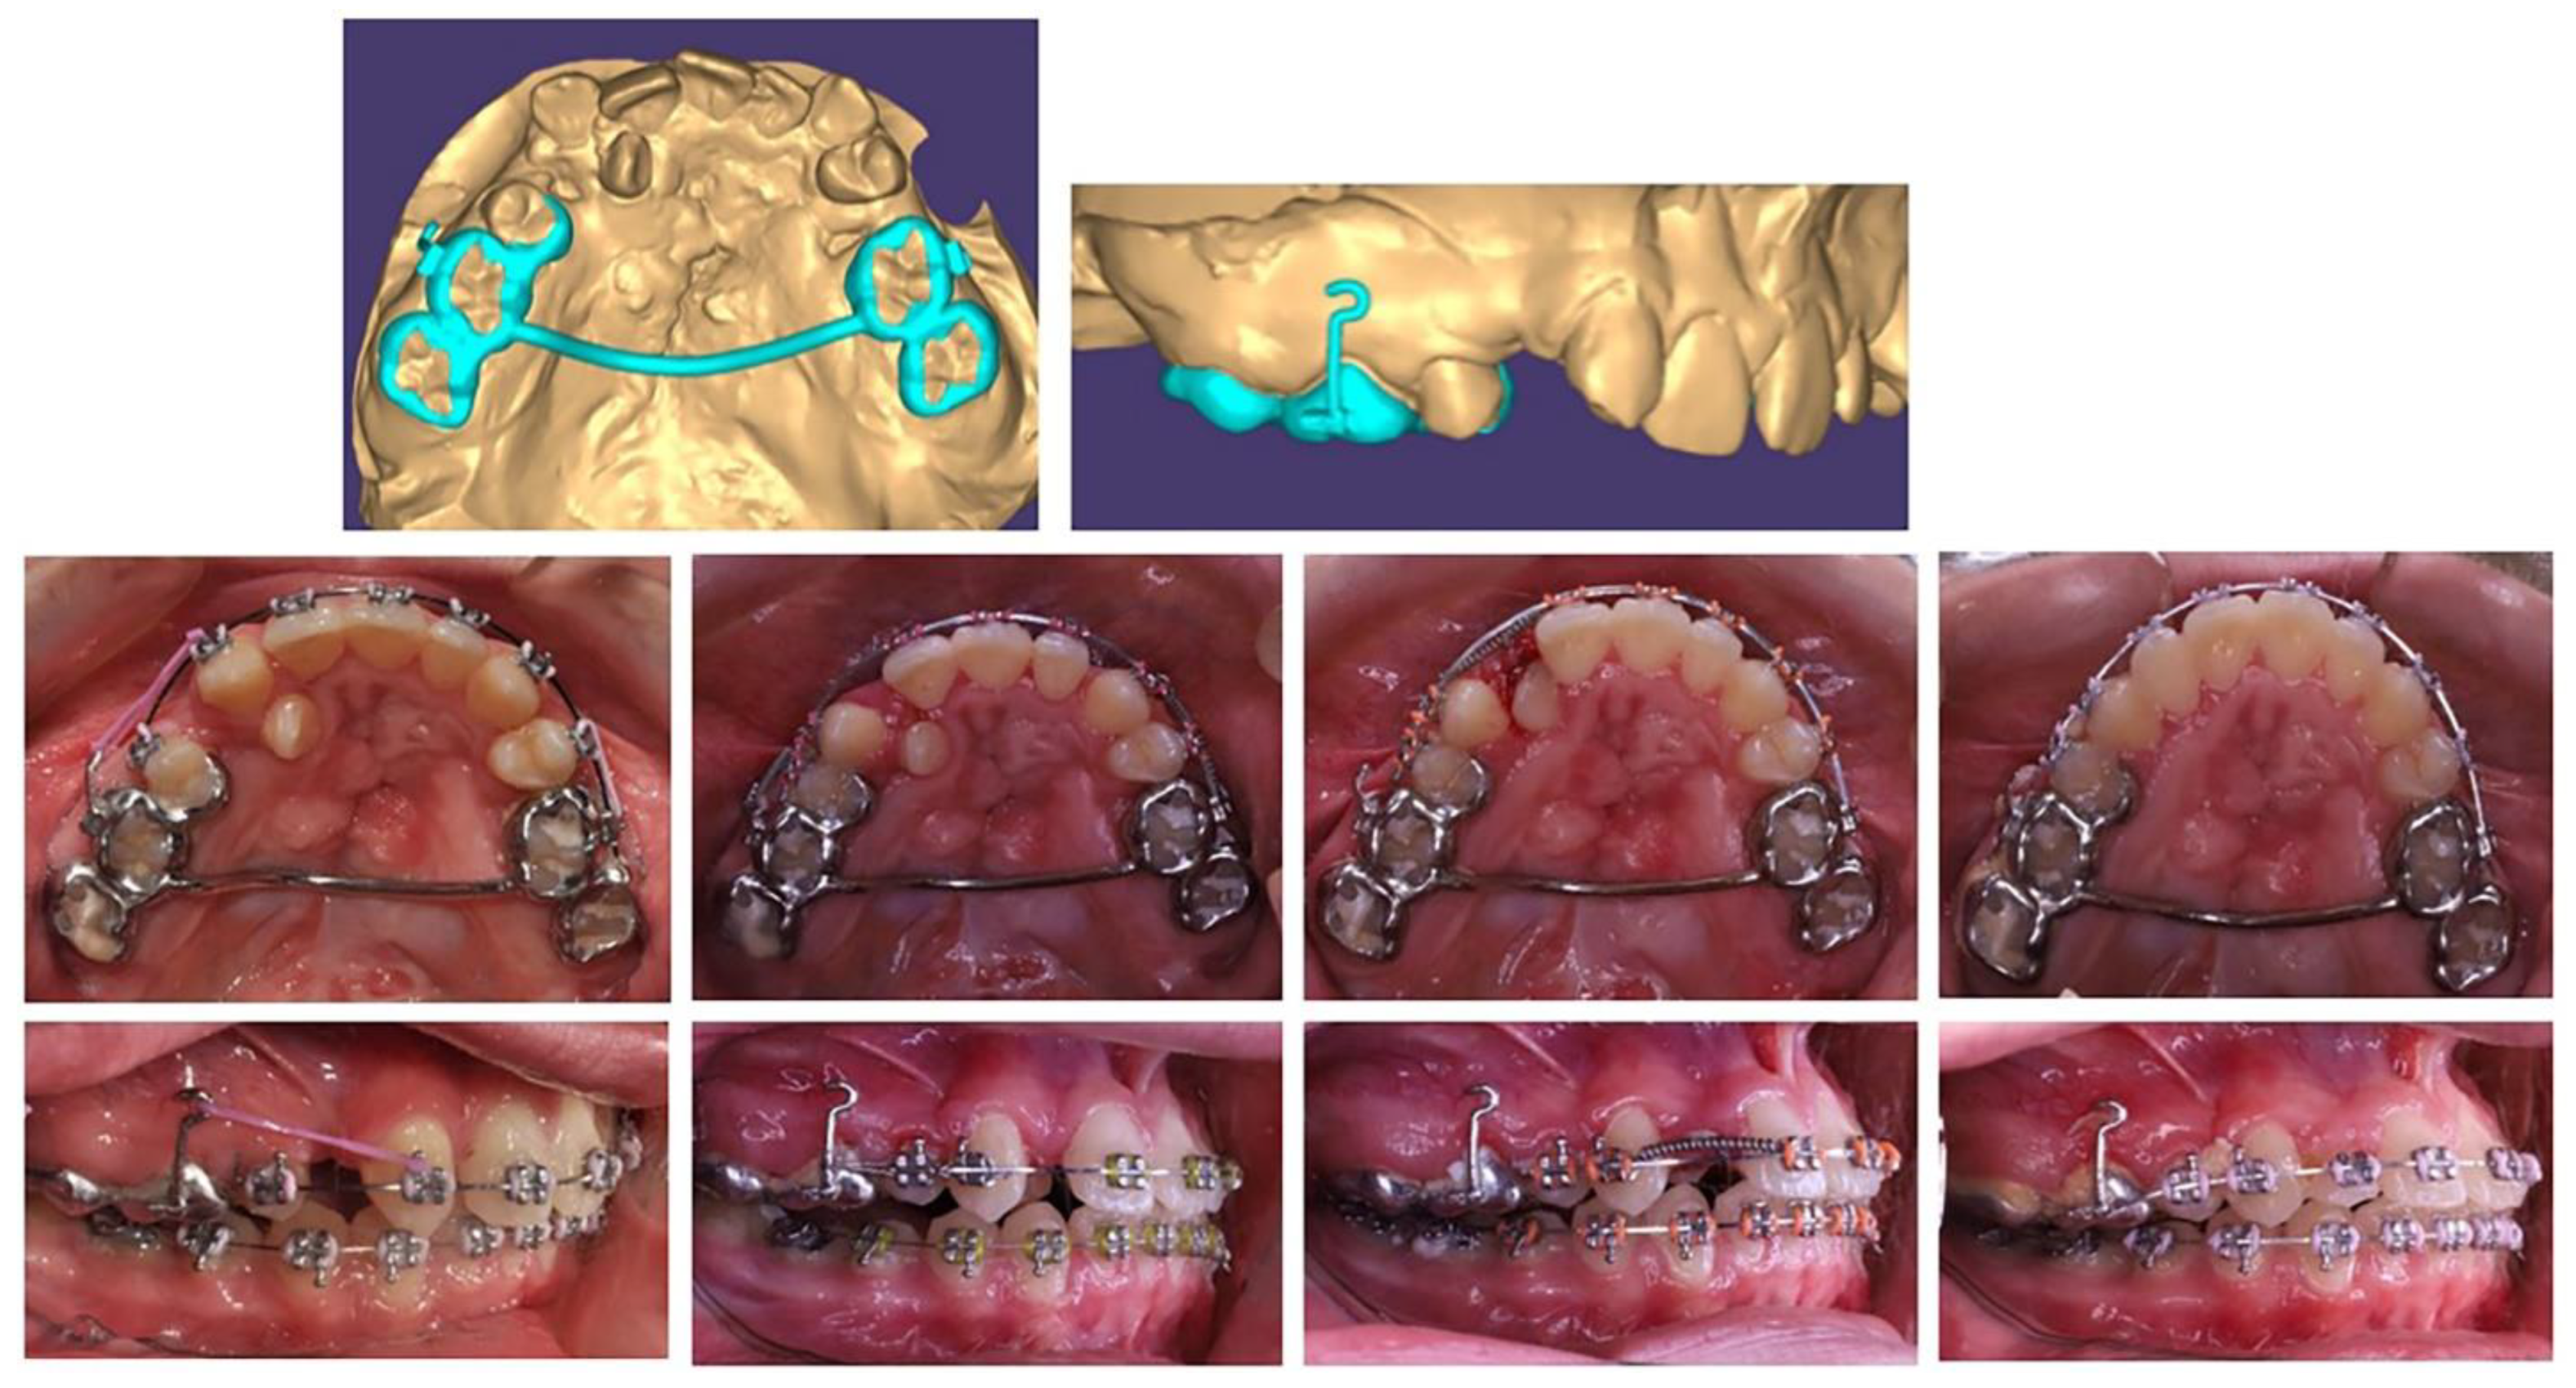

Medial movement of the lateral needs to be as lingual as possible along the highest part of the alveolar ridge to accommodate the canine germ, which is positioned more vestibular. Therefore, an anchorage point is needed to apply a medially directed force from the lingual (side). In this phase of mixed dentition, only the permanent first molars are stable. Therefore, the solution is a rigid lingual arch with a hook in the area of the central incisors, as a fulcrum to apply the force to straighten and move the lower right lateral.

Based on the patient's digital model, a lingual arch design was made with a hook in suitable location and direction for anchorage to tooth movement of the lower right lateral (Figure 2). The placed printed grids are maximally reduced, but at the same time stable enough to be anchorage. The patient adapted to it in a short time and the biomechanical system used showed a good result.

After moving the lateral incisor to its normal location in the lower dental arch, proceed to its levelling with the Utility arch, follow the eruption of the canine and both premolars. The treatment ended with the complete levelling of the dental arch.

Figure 2. Treatment progress in insertion of a lower right lateral in the dental arch, using a lingual arch support.